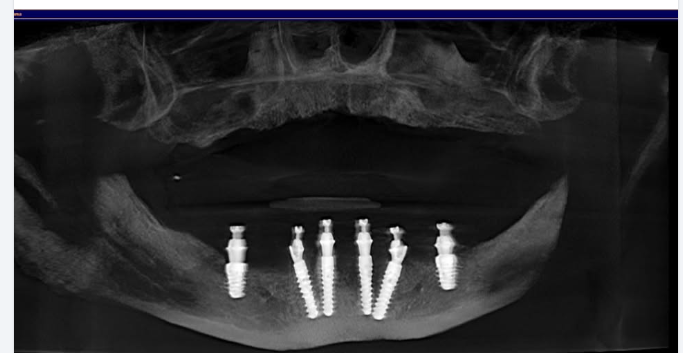

Hình ảnh 1 ca bị mất R34,37 được Bác sĩ tư vấn cắm Implant Mis C1 tại chi nhánh Huỳnh Văn Bánh, Phú Nhuận.

P/s: Image of a case with missing teeth R34,37 advised by the dentist for Mis C1 Implants at Huỳnh Văn Bánh branch, Phú Nhuận.